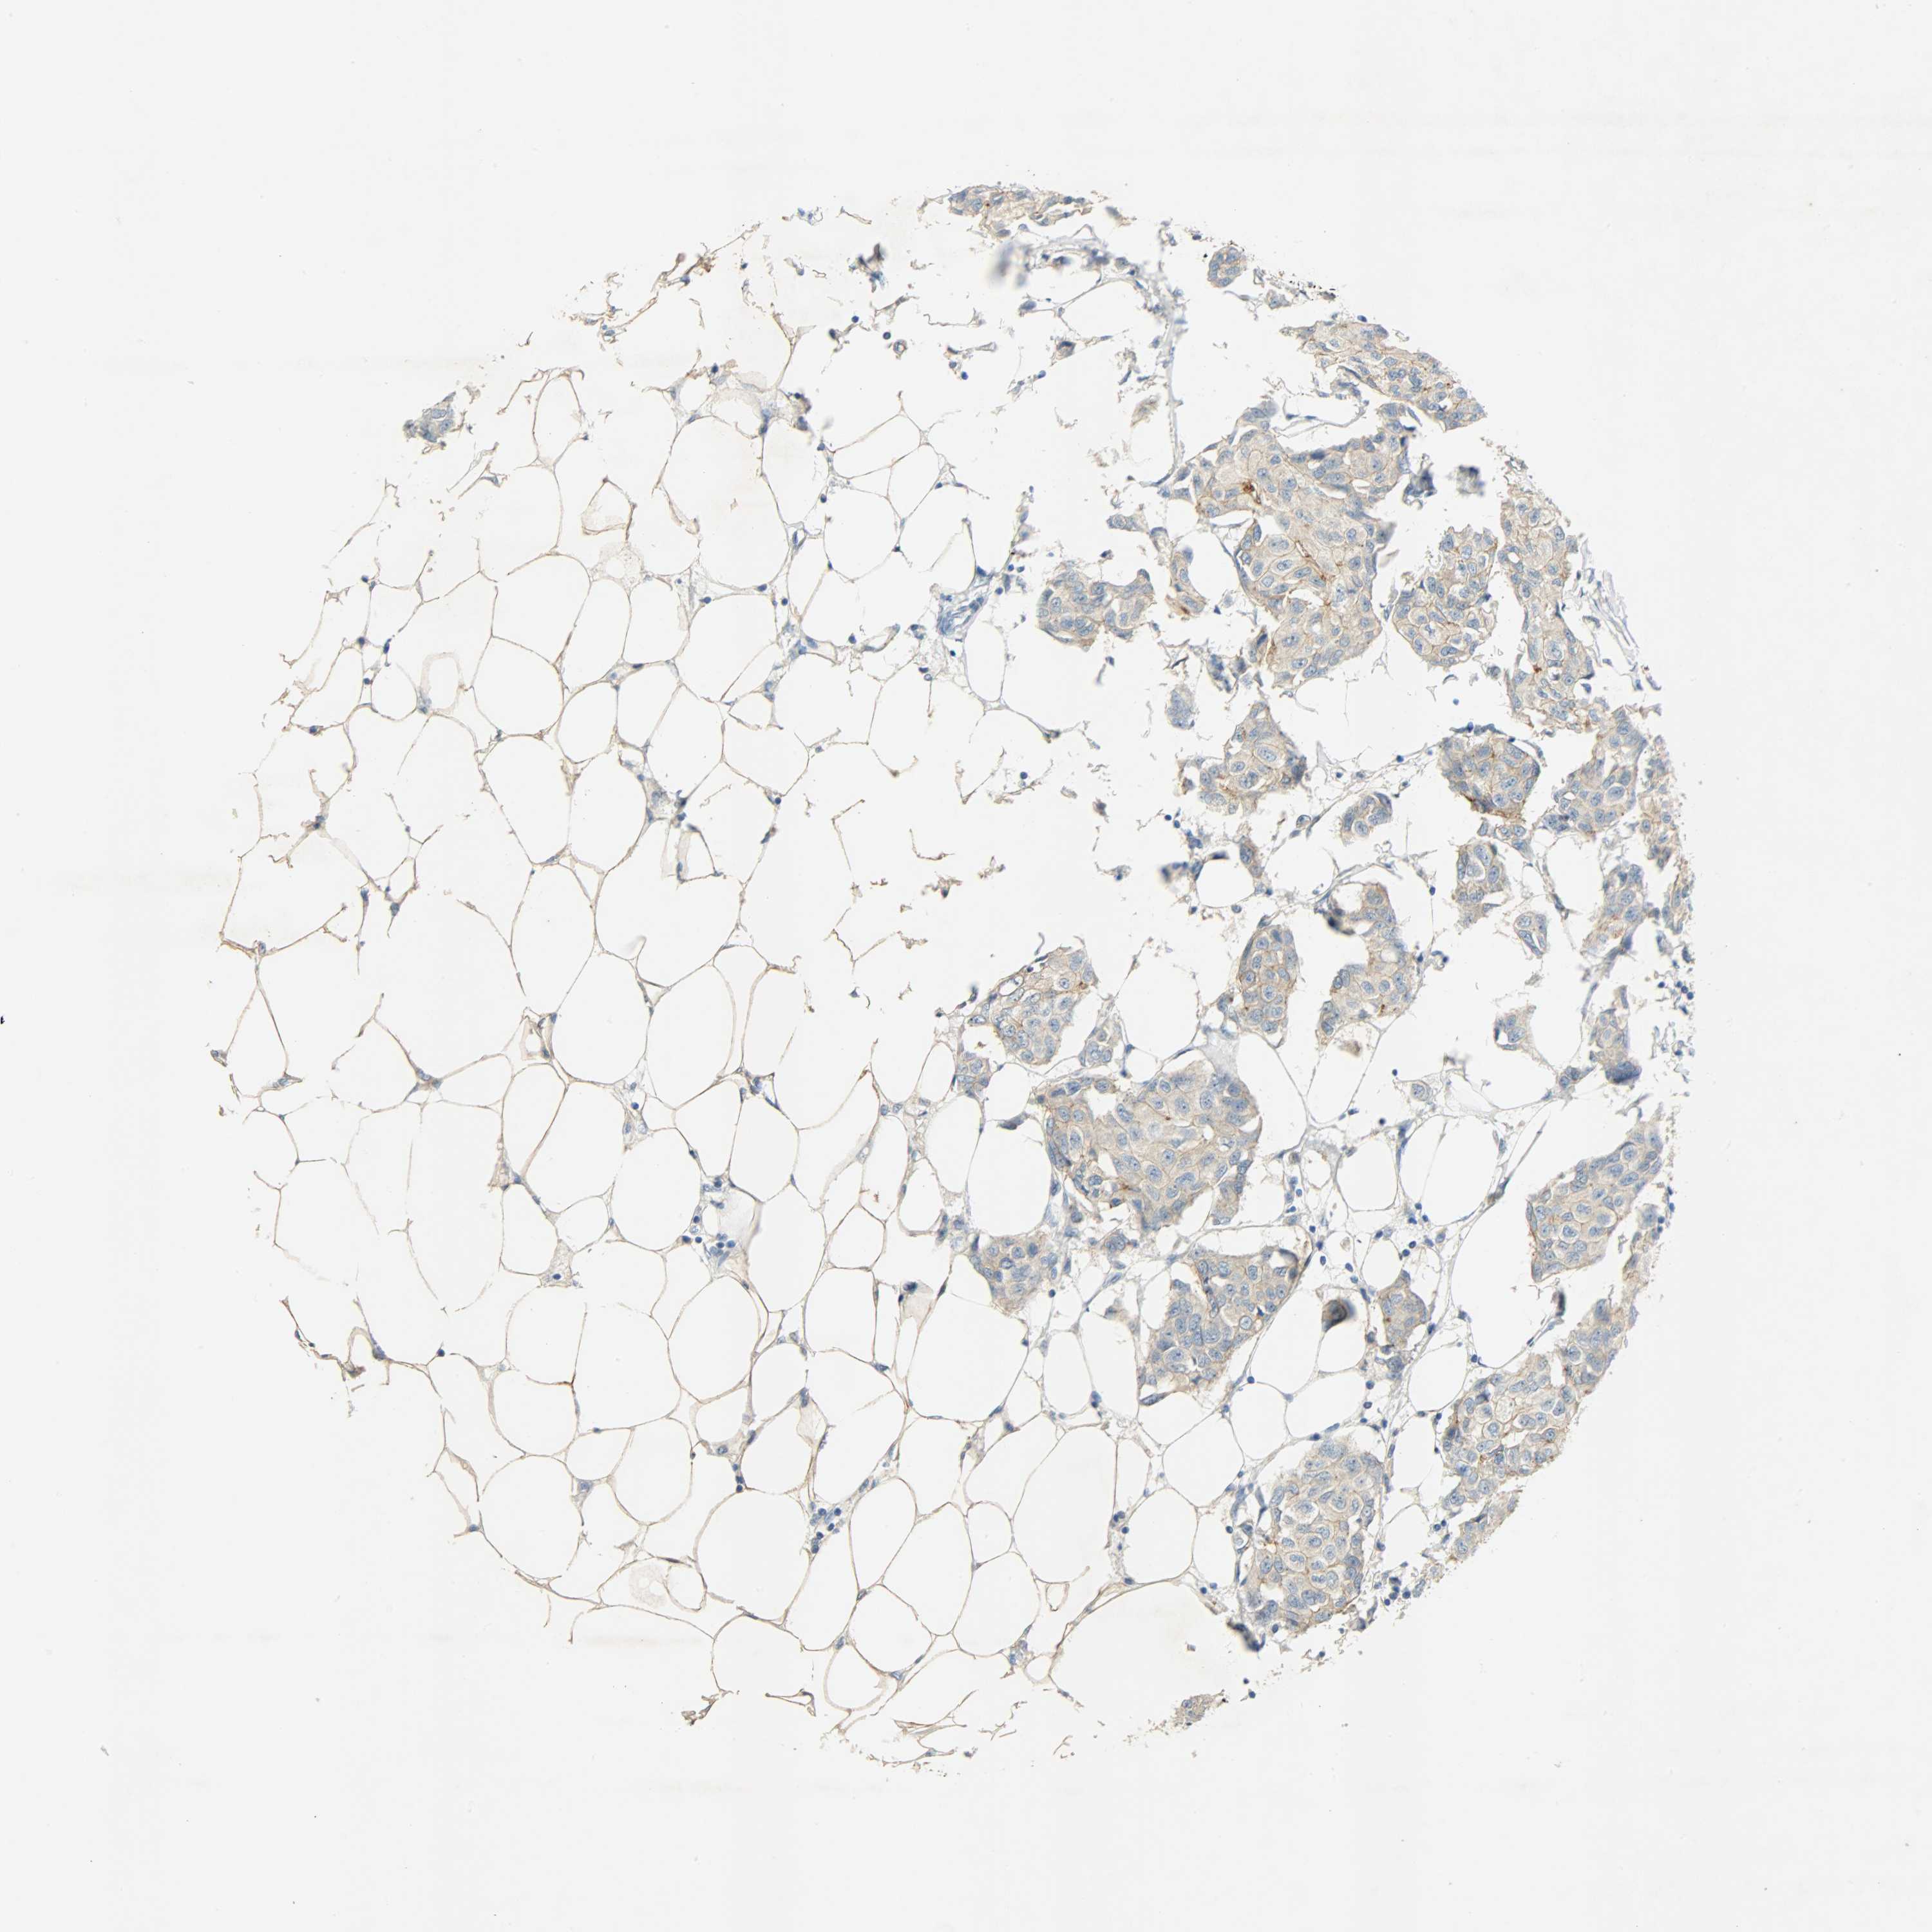

CANCER BREAST CANCER Show tissue menu

BRCA TCGA BRCA VALIDATION PROTEIN EXPRESSION